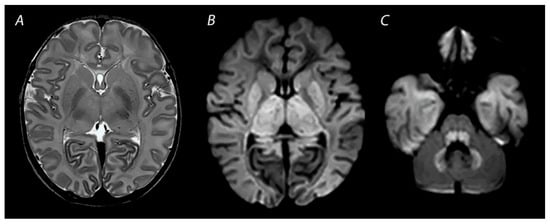

2.2. White Matter/Watershed (WM/WS) Predominant Pattern of Injury